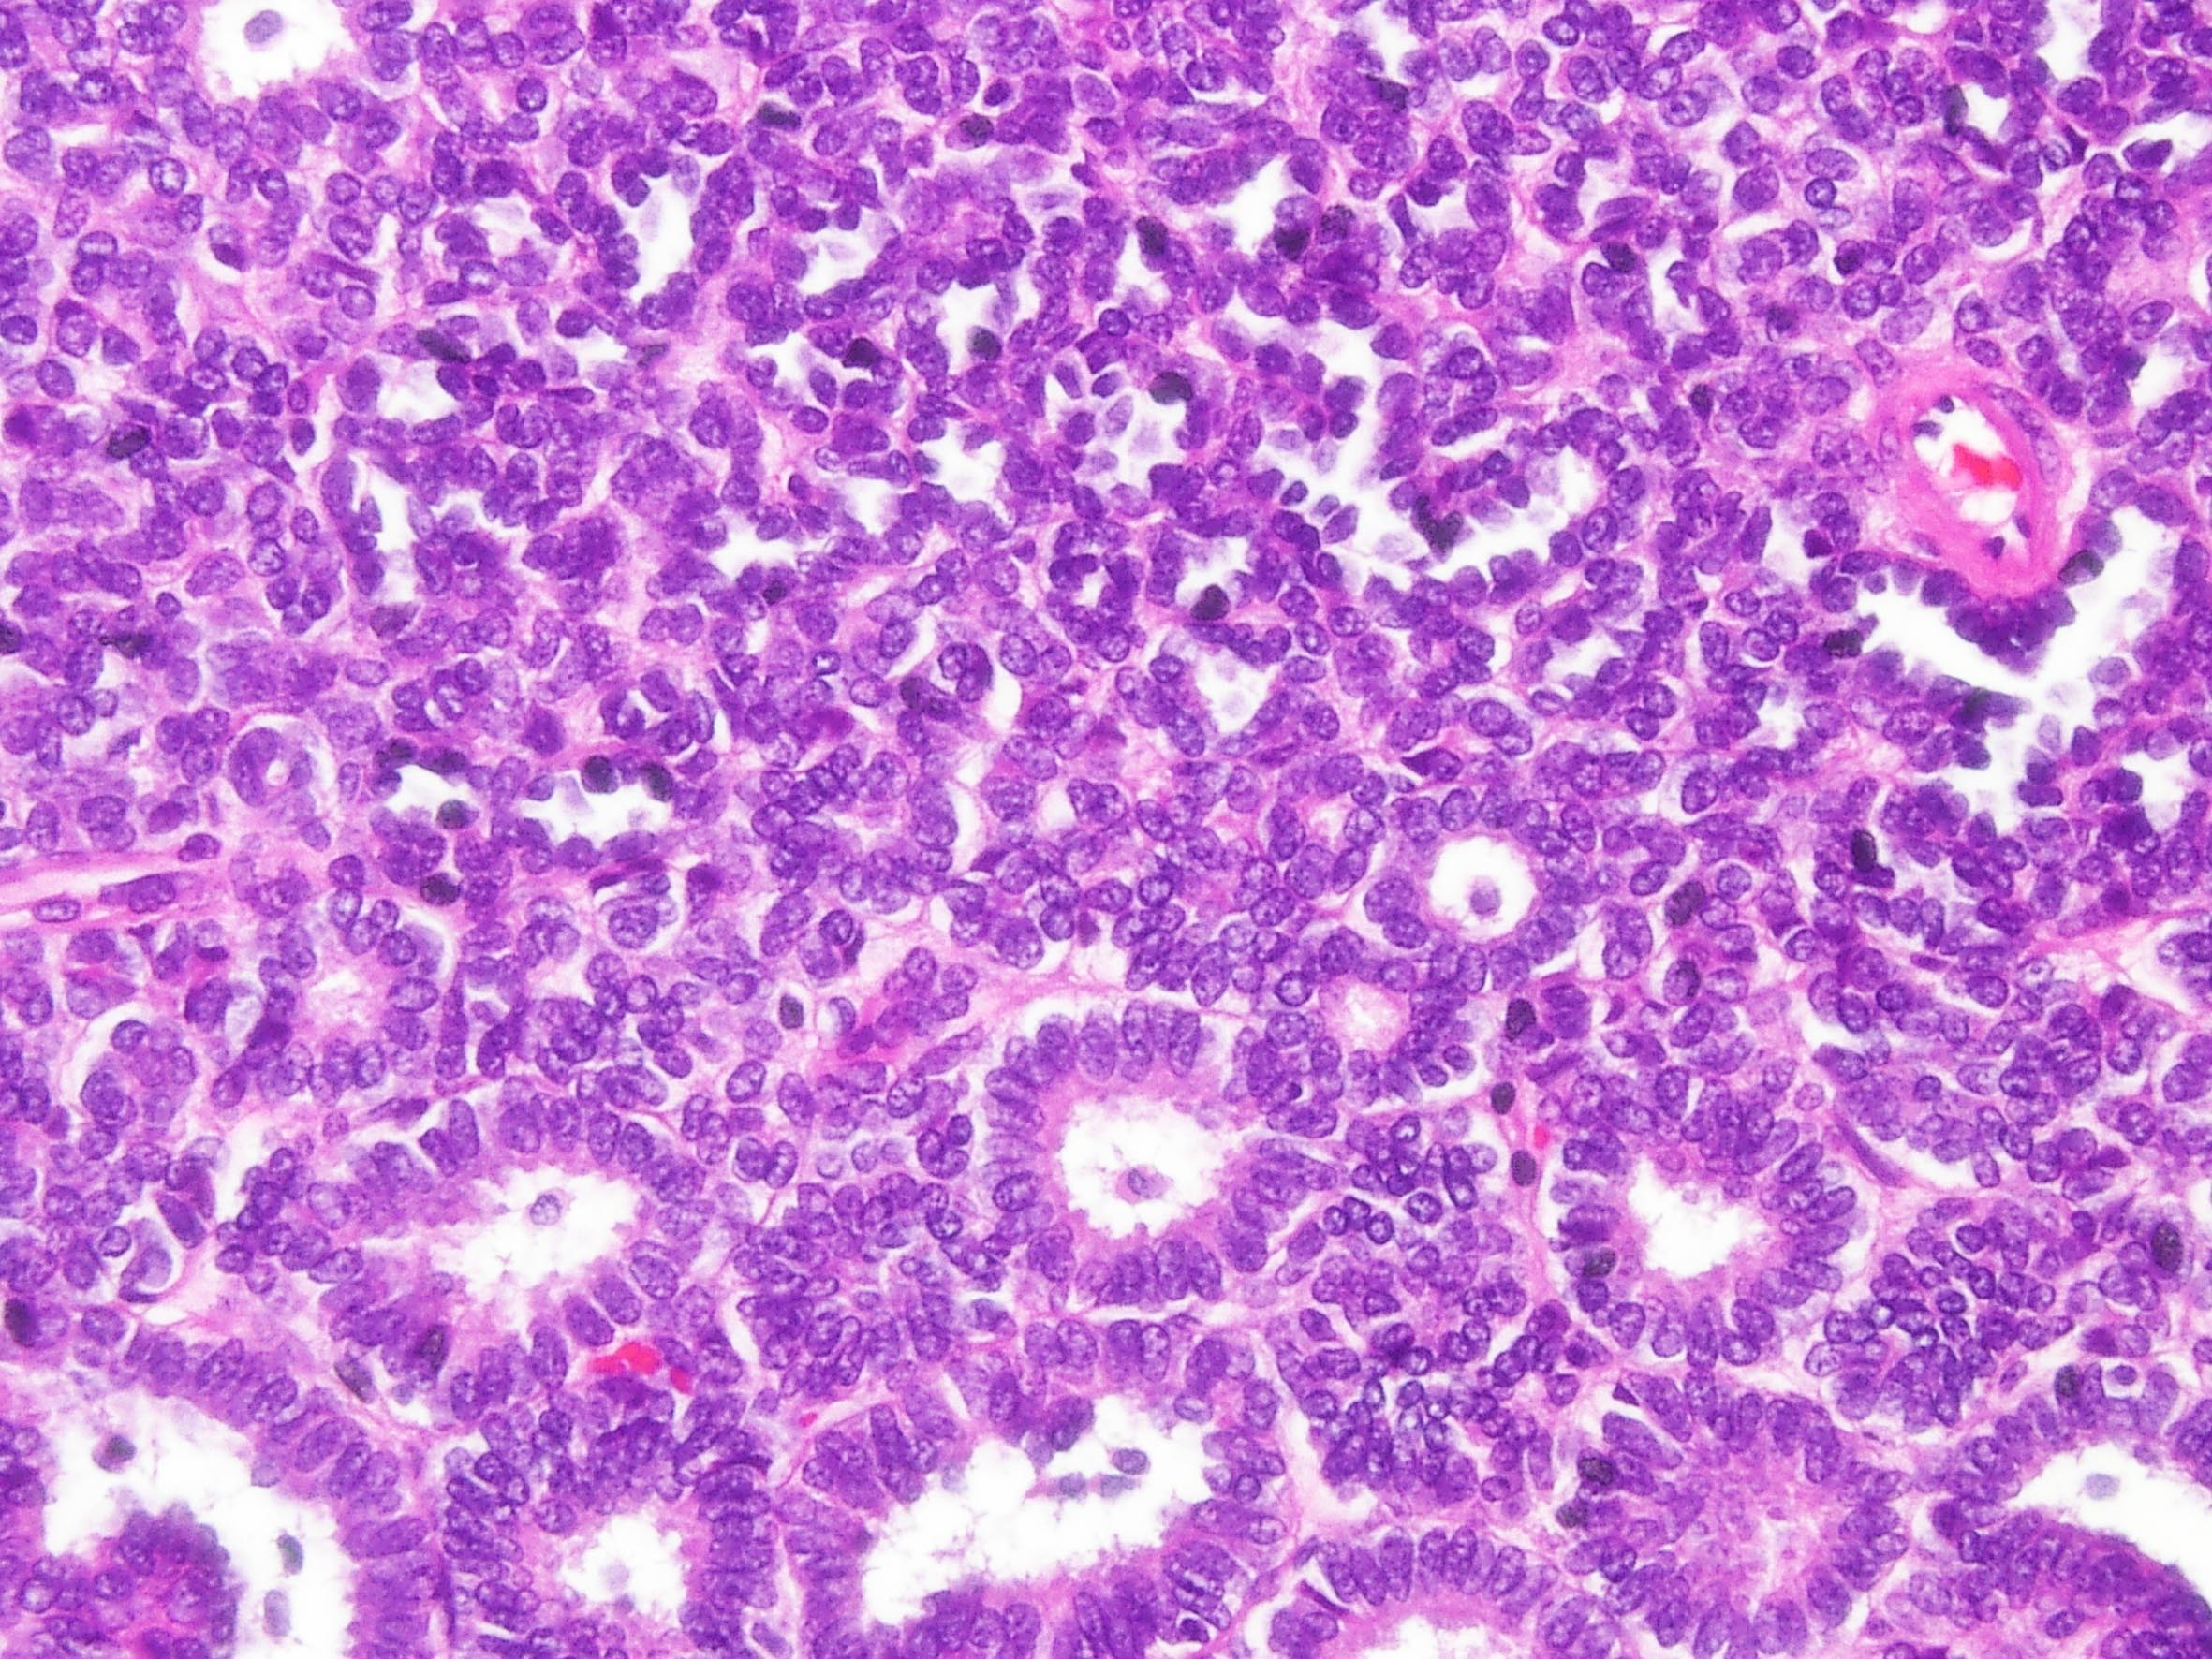

Case description (by case creator):

Metanephric adenoma